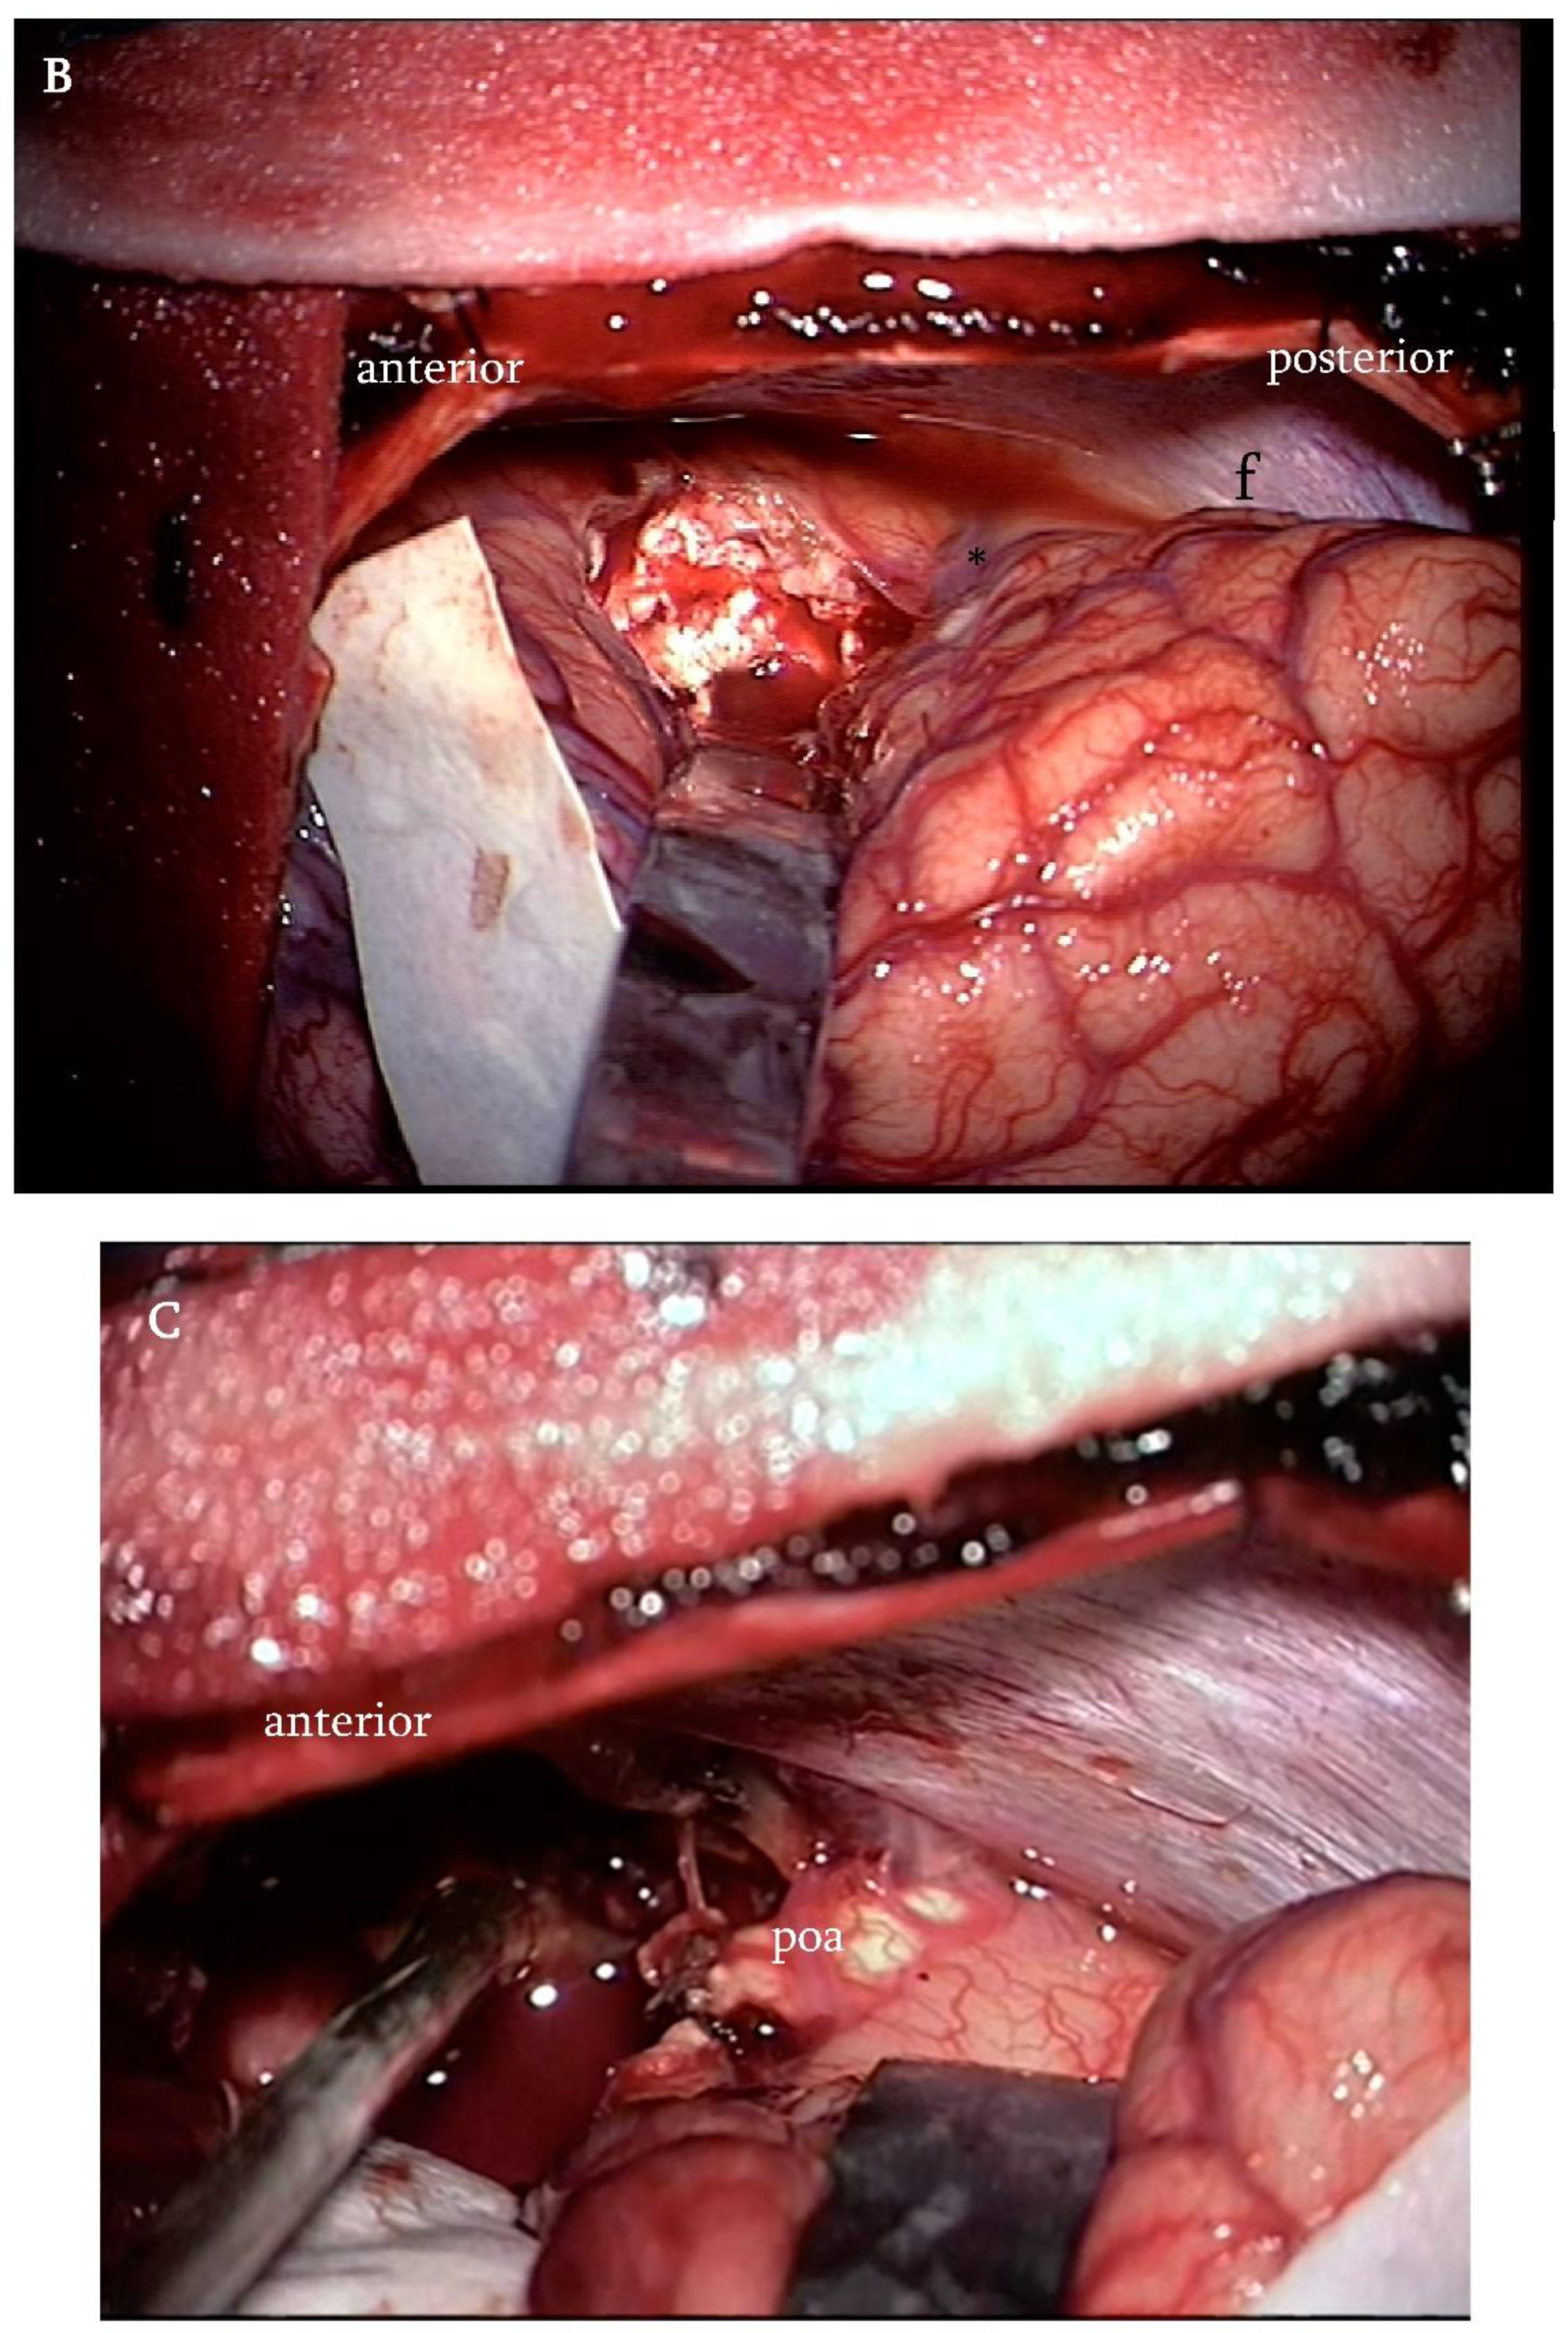

Figure 3. (A) Anatomic landmarks of the medial surface of the cerebral hemispheres. The precuneus is limited by the marginal ramus of the cingulate sulcus anteriorly (red dashed line) and by the parieto-occipital sulcus posteriorly (green dashed line). The cuneus comprises the area between the parieto-occipital sulcus and the calcarine sulcus (blue dashed line). In the IITA, the corticotomy (white circle) is performed just in front the deepest portion of the parieto-occipital sulcus, adjacent to the cingulum. (B) Intraoperative photographs showing the site of the corticotomy just in front of the parieto-occipital sulcus (asterisk) (f: falx). (C) The parieto-occipital artery (poa) identifying the parieto-occipital sulcus.

A 10 to 20 mm corticotomy is performed just in front of the inner portion of the parieto-occipital sulcus adjacent to the cingulate gyrus but without violating it under microscopic magnification. Brain retractors are placed. Gentle spreading of the margin of the corticotomy opens the corridor toward the atrial cavity. (Figure 3).